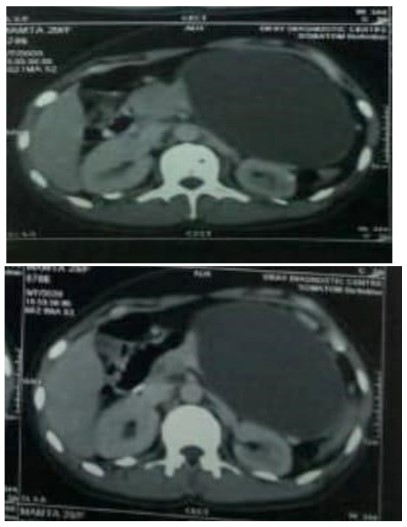

On imaging studies at our hospital, CT of chest had no specific abnormality while CT abdomen showed very large well defined encapsulated cystic lesion measuring 10.4 x 9.2 x 11.2 in region of body and tail of pancreas with mild splaying of pancreatic tissue in body region. Fluid attenuation contents were seen with tiny mural nodule along inferior surface of the cyst. Surrounding fat planes were intact, reteropancreatic splenic vein was attenuated with multiple collaterals in gastrosplenic ligament and perigastric lesion along superior and lateral aspect of cyst. Spleen showed mild splenomegaly with few small hypodense areas along superior and mid lower pole small infarcts, few small retroperitoneal and mesenteric lymph nodes were seen.

Figure 1 & 2: CT abdomen showed large well defined cystic lesion involving body and tail of pancreas with tiny mural nodules.